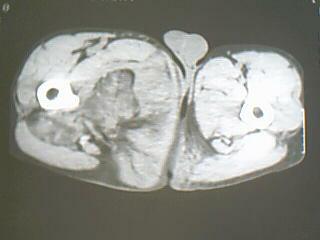

患者 男 34岁 右腿肿物。98年右侧外伤致股骨骨折,手术治疗,2001年二次手术(取钢板),发现大腿内侧有鸡蛋大小样肿块,无明显疼痛不适,2007年开始发现肿物明显增大,无发烧,无红肿。

病灶巨大,内见脂肪影,考虑软组织肿瘤,脂肪肉瘤?恶性纤维组织细胞瘤?

右侧大腿内侧肌间含脂性巨块,密度不均,内见软组织成分及条管状钙化,错构瘤伴出血?真性或假性脂肪瘤

右大腿内后侧巨大混杂密度软组织肿块似与邻近正常组织分界尚清,增强看看肿瘤血供情况再做下一步打算吧,现在猜测是啥依据尚少,叫真儿的就穿刺活检。